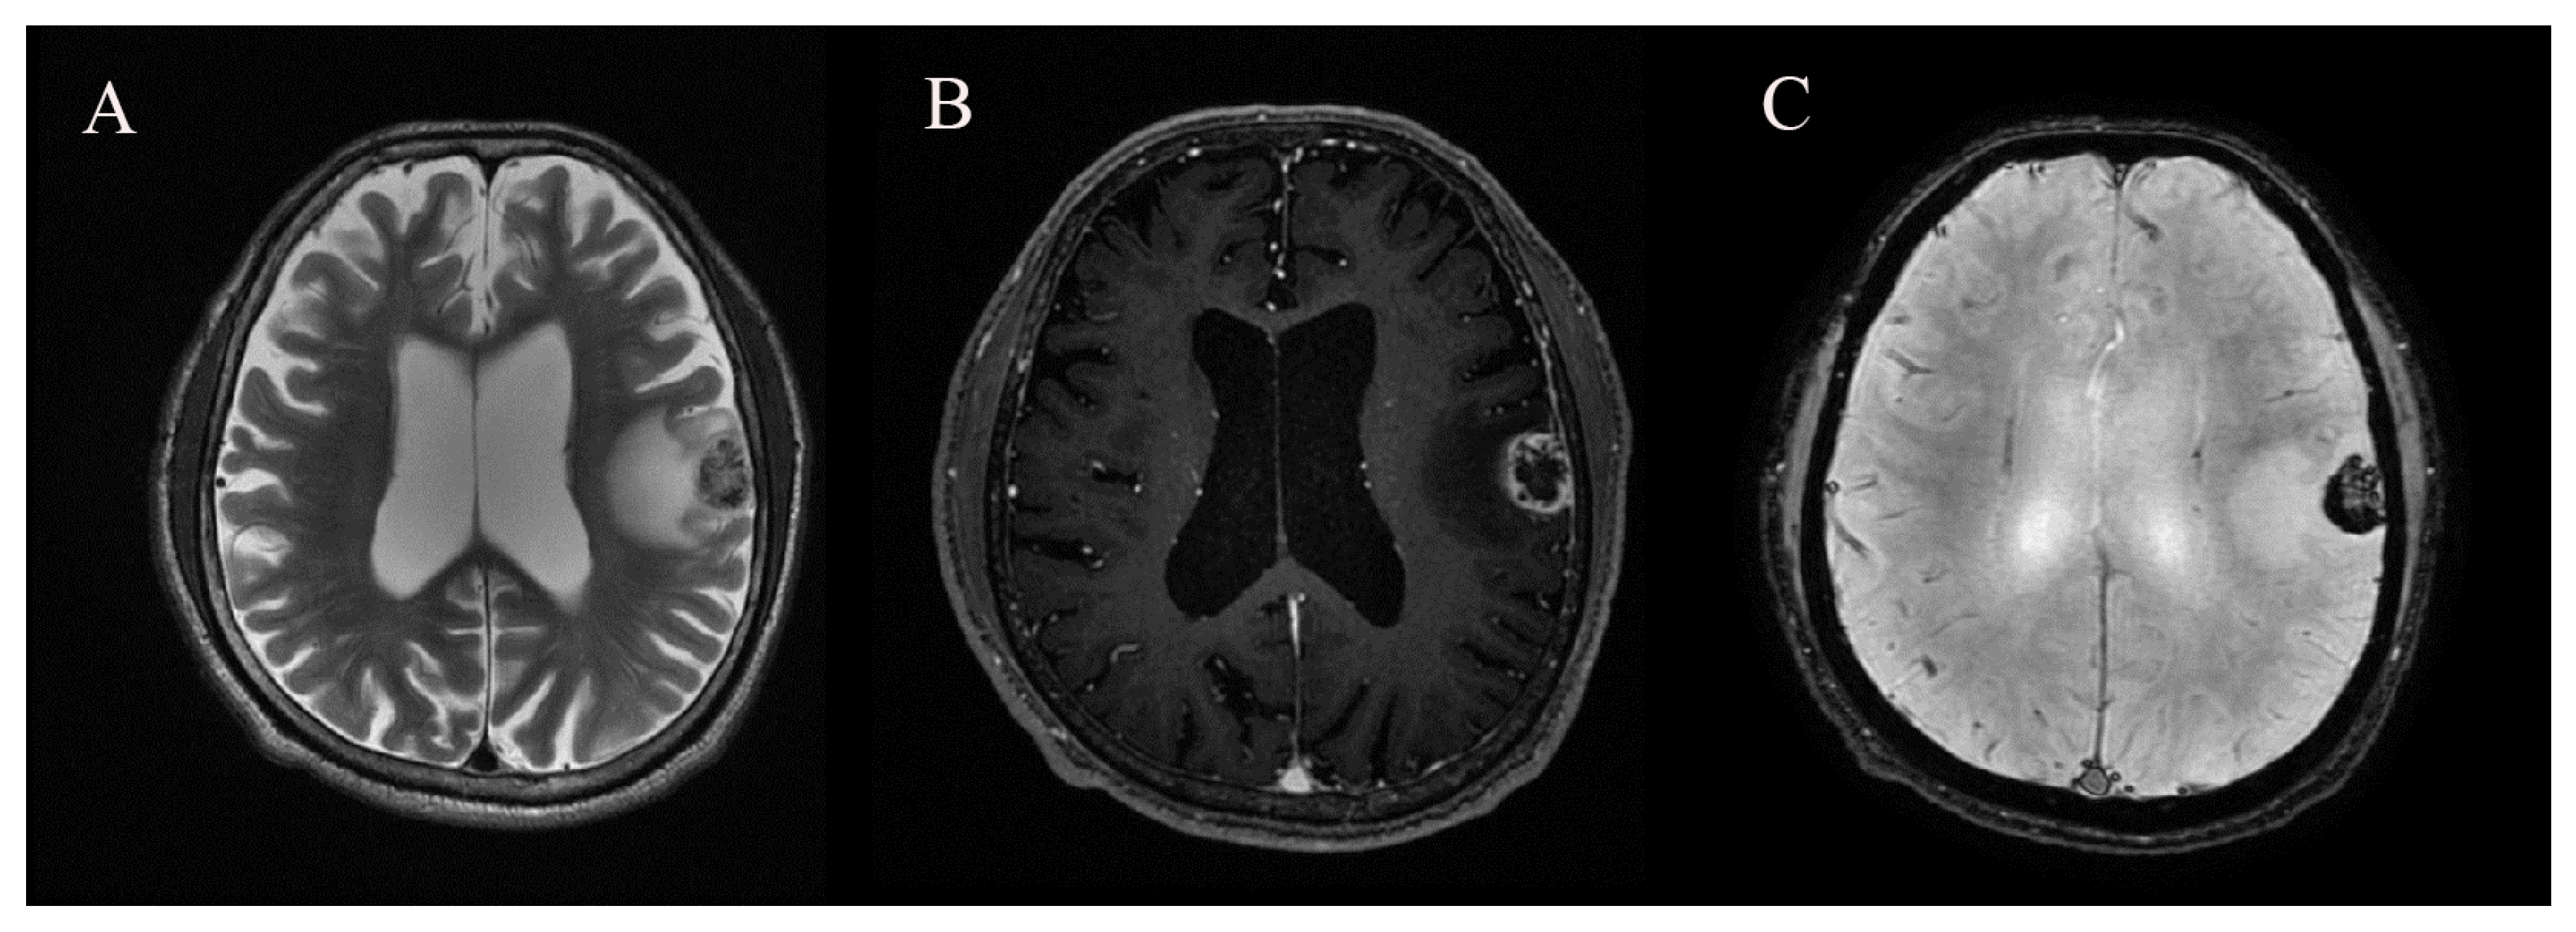

2.2. MRI and Image Analysis